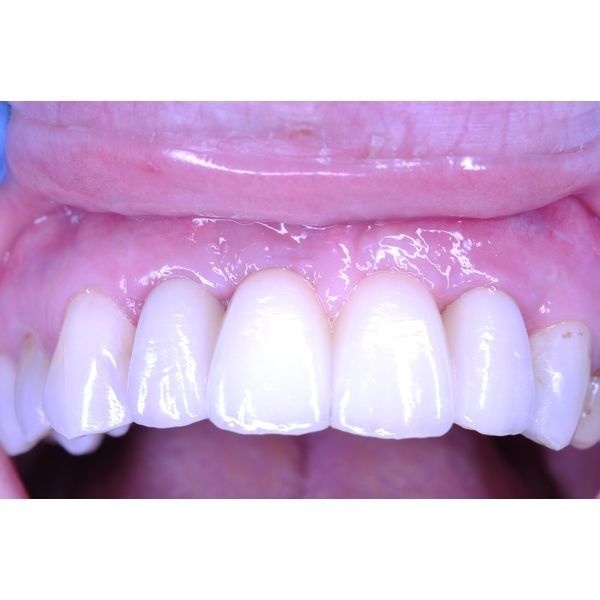

На следующем приёме ей удалили временный протез и установили циркониевый мост.

Сначала пациентка отмечала незначительный отёк и синяк, но через некоторое время они сошли на нет. Женщина осталась довольна лечением. Ей рекомендовали приходить на осмотры 1–2 раза в год, использовать ирригатор при проведении домашней гигиены и сделать контрольные КТ-снимки через 6–12 месяцев.

Цирконий считается универсальным металлом для применения в медицинской отрасли, так как он не вызывает контактную аллергию. Это особенно важно при изготовлении коронок и мостов, которые ставят в челюстно-лицевую область, граничащую с жизненно важными органами.

Циркониевые конструкции идеально точно садятся на своё место, что влияет на срок службы зуба и конструкции. Кроме того, при использовании циркония у пациента есть возможность выбрать необходимый оттенок, который будет полностью совпадать с его родными зубами.